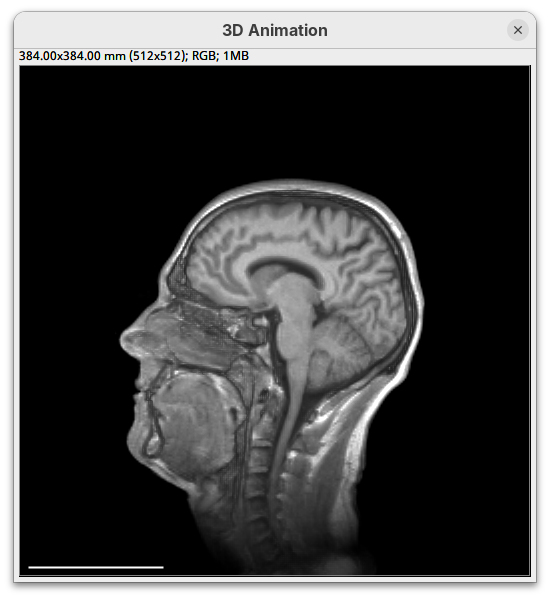

We will begin by visualizing an MRI dataset of a human head that is bundled in Fiji.

- Go to

File>Open Samples>T1 Head (16-bits).

BigDataViewer

BigDataViewer (Pietzsch et al. 2015) is one of the most important tools for visualizing large, multidimensional datasets. It provides a simple and intuitive interface and shortcuts to swiftly navigate through your sample even on a regular laptop. This is possible because of the underlying file format used by BigDataViewer: the XML/HDF5 combo. Therefore, before opening the plugin, we must convert our dataset.

Plugins>BigDataViewer>Open XML/HDF5and select thet1-head.xml.

The BigDataViewer interface will open showing an optical section of the head sample.